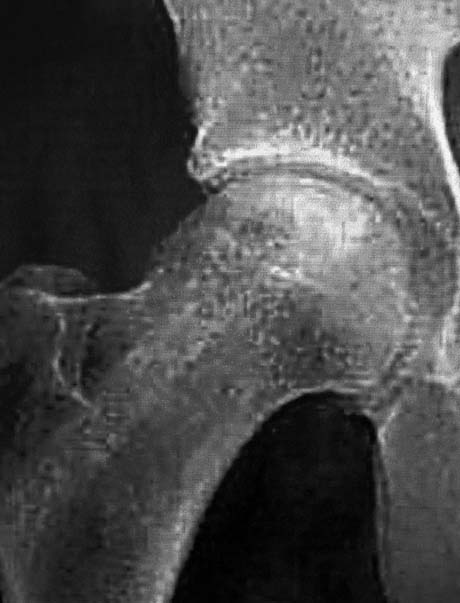

Female 51 years old with pain in the right hip from 3 months ago. Examination MRI showed osteonecrosis of the femoral head right.

FIVE MONTHS POST-OP

Magnetic resonance imaging of the hip after 5 months post-op and the injection of stem cells. Osteonecrosis of the femoral head has subsided completely. The patient is fully cured.

Hip X-ray 5 months post-op

After surgery on the patients right hip the symptoms began to subside immediately. The patient gradually weight bearing the right limb, and five months after it is fully functional without any pain and stiffness in the hip joint.